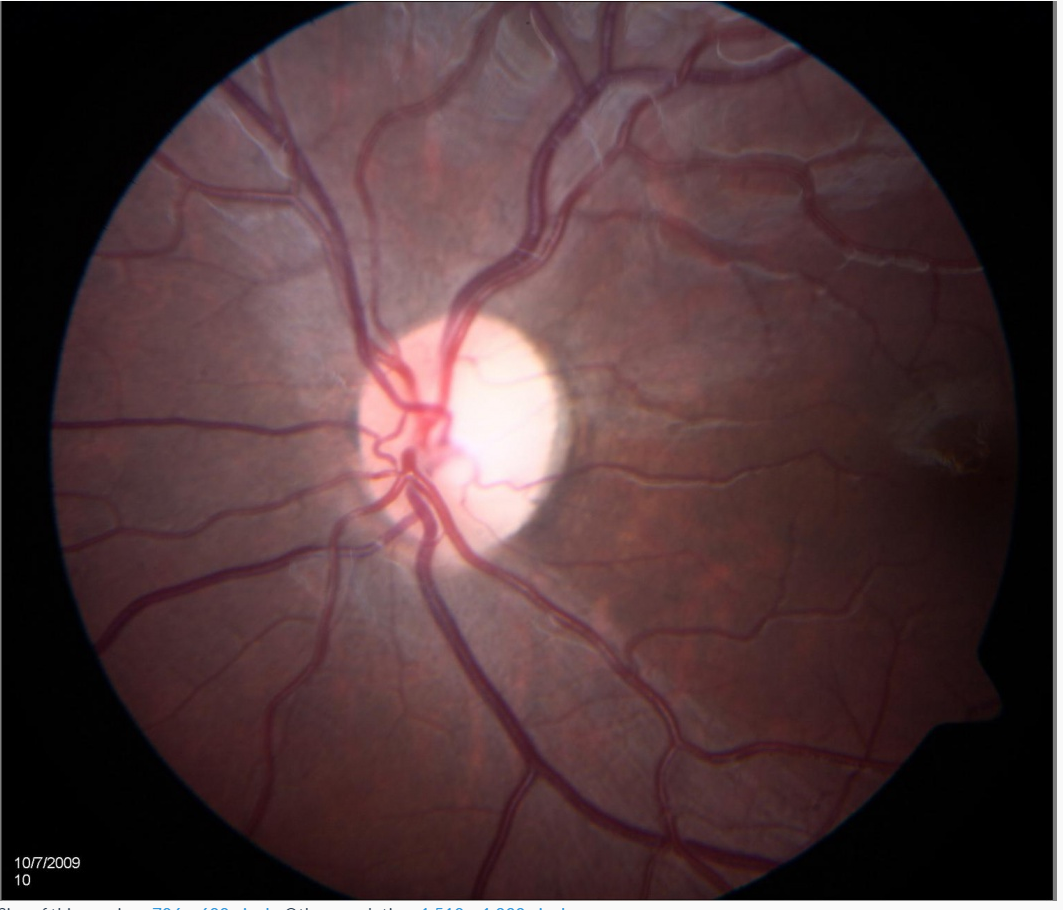

Optic atrophy